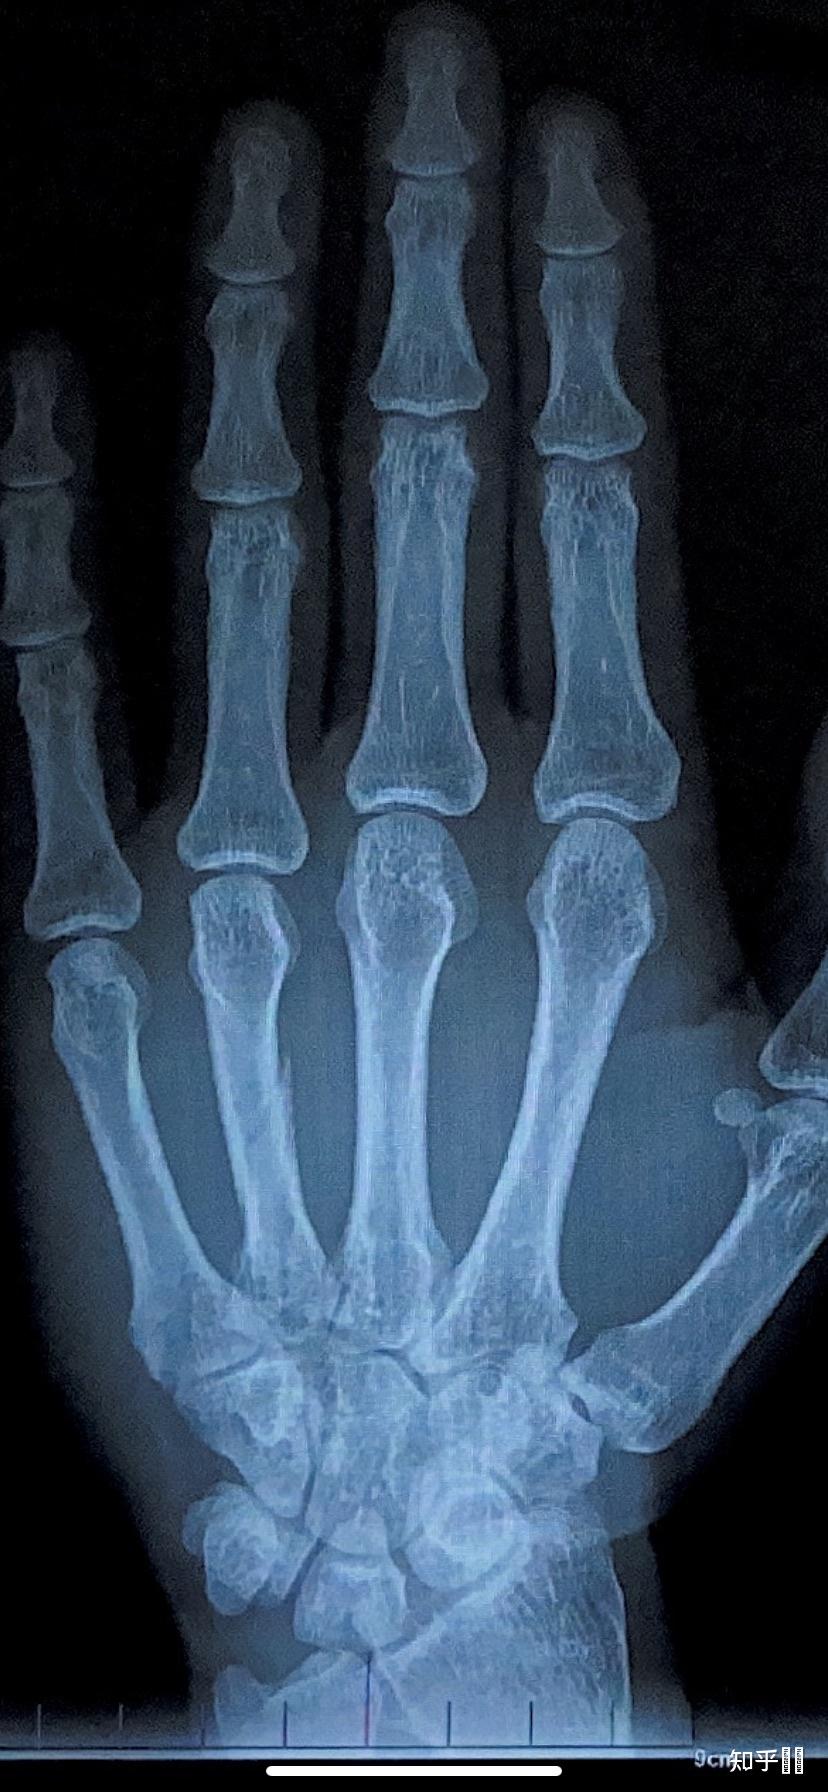

右手第四掌骨骨折

图片尺寸768x1024